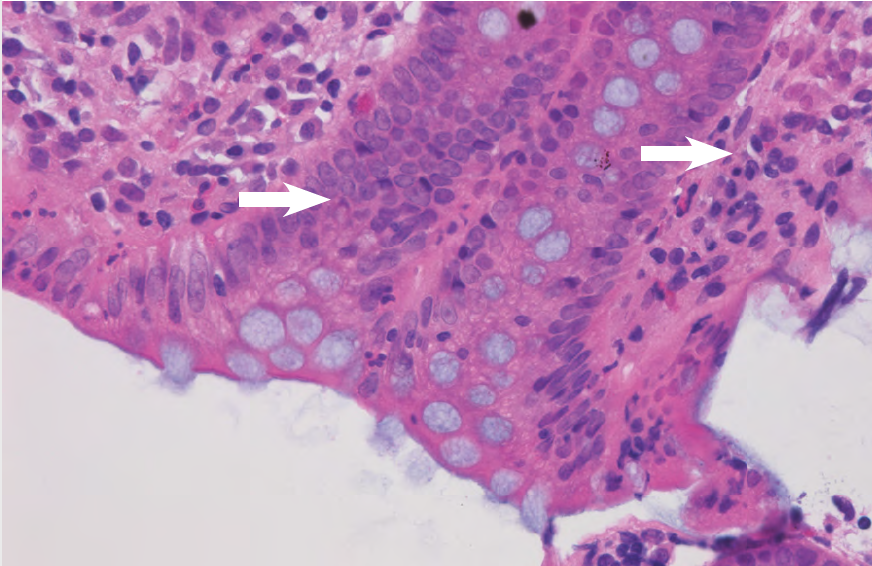

Příklad: Bazofilním materiálem přítomným v granulomu zobrazeném na obrázku 14 je vápník. Velké množství se při krájení roztříštilo a z řezu vypadlo. Tato fotografie byla pořízena z nejzachovalejší části řezu. Povrchové odvápnění (řešení 6) umožnilo získat několik soudržných řezů. Pokud by zde krok odvápnění zahrnut nebyl, přineslo by opětovné zpracování vzorku jen malé zlepšení.

Obrázek 14: Granulom obsahující bazofilní vápník (H&E).